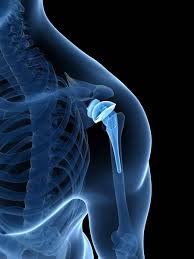

One of the key advancements in joint replacement surgery is the development of improved materials for prosthetic joints. In the past, joint replacements were made primarily of metal and plastic components. Today, advancements in biomaterials have led to the creation of highly durable and biocompatible materials like ceramic and metal alloys. These materials mimic the natural joint’s structure and function, providing a more natural range of motion.

Every patient’s anatomy is unique, and the development of customized implants has allowed for a more personalized approach to joint replacement surgery. Using advanced imaging and 3D printing technology, surgeons can create implants that match the patient’s specific joint dimensions, leading to a better fit and improved functionality.